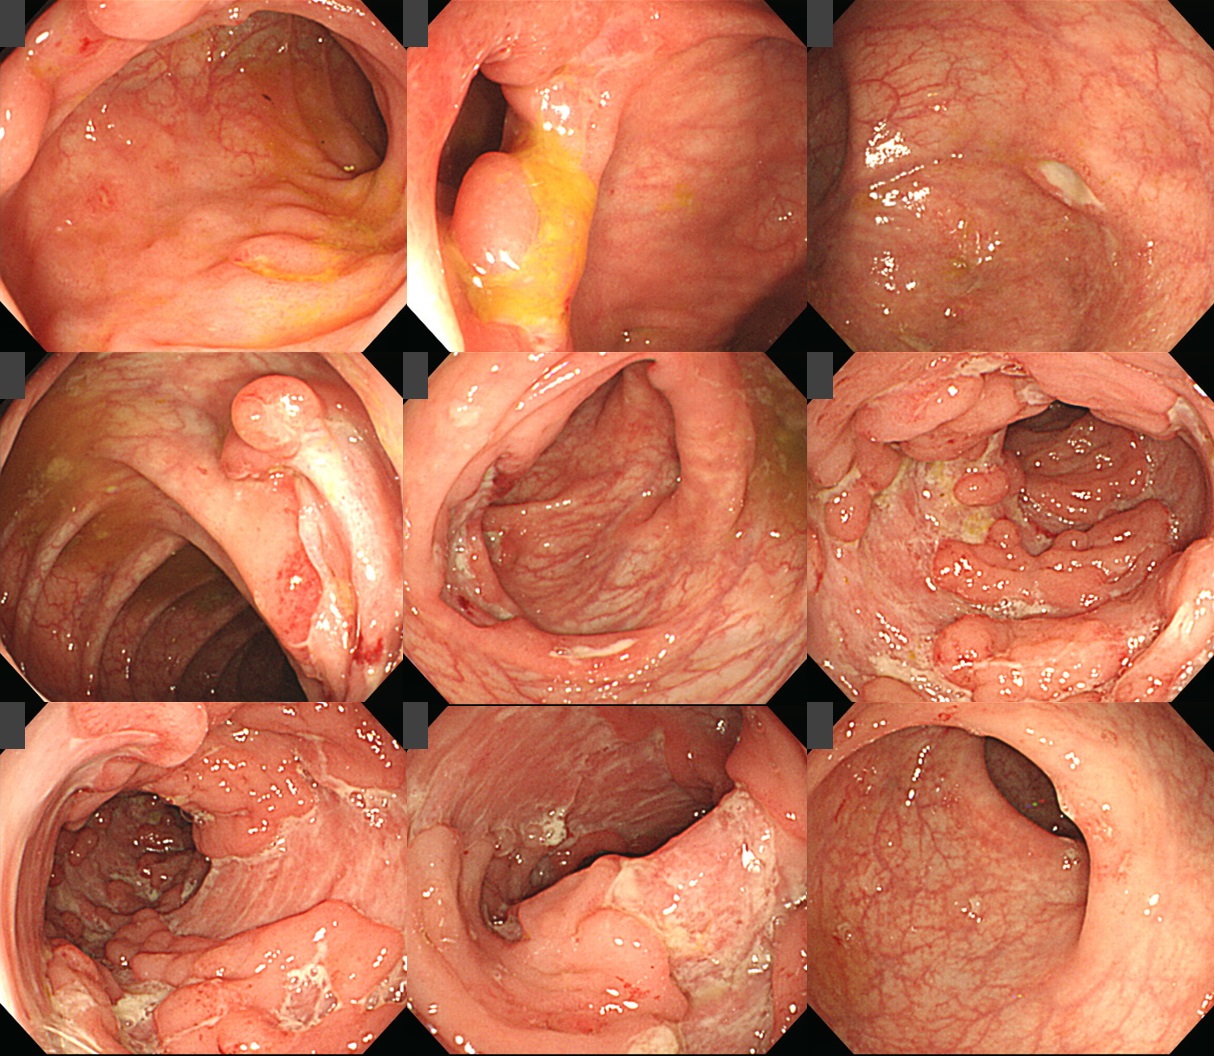

³»½Ã°æ ¼Ò°ß:

A) ¸»´Ü ȸÀåÀÇ Ç¥¸éÀÌ ´Ù¼Ò unevenÇϸç 0.2cmÀÇ erosion (= aphthous ulcer)µéÀÌ ¸î °³ °üÂûµÈ´Ù.

B) IC valve°¡ deformed µÇ¾î ÀÖÀ¸¸ç IC valveÀÇ circumference¸¦ µû¶ó ±æÂßÇÑ shallow ulcer°¡ ÀÖ´Ù. UlcerÀÇ edge´Â sharp, irregularÇÏ¸ç ¹Ù´ÚÀº ÆòźÇÏ´Ù.

C) Cecum¿¡ 0.5cmÀÇ ovoid shallow ulcer°¡ ÀÖ´Ù. Edge´Â sharpÇϸç marginÀº heaped up µÇ¾î ÀÖ°í ¹ßÀûÀ» º¸ÀδÙ.

D,E) ¿øÀ§ºÎ »óÇà°áÀåºÎÅÍ È¾Çà°áÀå¿¡ ±ºµ¥±ºµ¥ ÀåÀÇ È¾ÃàÀ» µû¶ó Å©°í ÀÛÀº ±Ë¾çµéÀÌ °üÂûµÈ´Ù.±Ë¾ç°ú ±Ë¾ç »çÀÌÀÇ Á¡¸·Àº ºñ±³Àû Á¤»óÀÌ´Ù.

F,G,H) S °áÀå¿¡ ´Ù¼öÀÇ longitudinal ulcer µé°ú cobble stone appearance°¡ °üÂûµÈ´Ù. °¢°¢ÀÇlongitudinal ulcer´Â circumferenceÀÇ 10-20%¸¦ Â÷ÁöÇÒ Á¤µµ·Î ³Ð°í ±íÀ¸¸ç ¹Ù´ÚÀº ÆòźÇϰí edge´Â sharpÇÏ´Ù. Longitudinal ulcer »çÀÌÀÇ Á¡¸·Àº ÀϺΠ¹ßÀû°ú ºÎÁ¾À» º¸ÀÌ¸ç ºÒ±ÔÄ¢ÇÑ edge¸¦ °¡Áø longitudinal ulcer¿¡ ÀÇÇÏ¿© geographicÇÑ ¾ç»óÀ» º¸¿© À졧 cobble stone appearance¸¦ º¸À̰í ÀÖ´Ù.

I) Á÷ÀåÀº ´ëºÎºÐ Á¤»ó Á¡¸·À̳ª ÀÛÀº ¾ÆÇÁŸµéÀÌ ¸î °³ °üÂûµÈ´Ù.

³»½Ã°æ Áø´Ü: Å©·Ðº´, ¸»´Ü ȸÀå°ú ´ëÀå, ¿°ÁõÇü